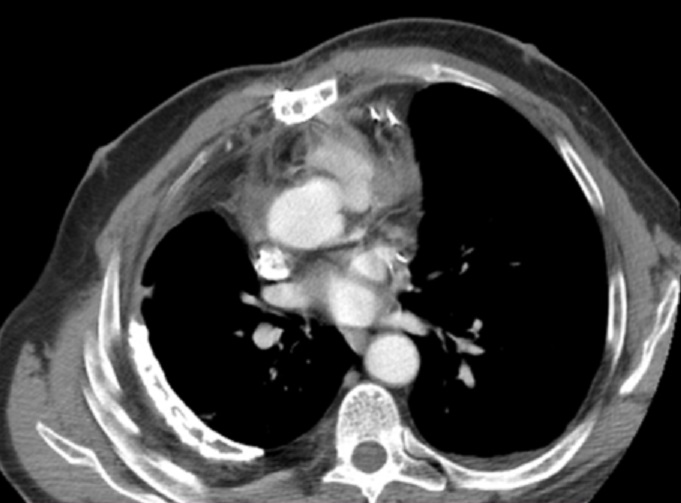

Image radiologique TDM en coupe TDM d'une

mesothelioma de la plevre du poumon gauche . Aspect

radiologique est epaissisement diffuse isodensite ,

homogene à bord viscerale est nette et irregulier ,

rehaussement legere de contrast intraveineuse .

Coupe TDM axiale fenetre madiastinale avec contrast

intraveineuse . |